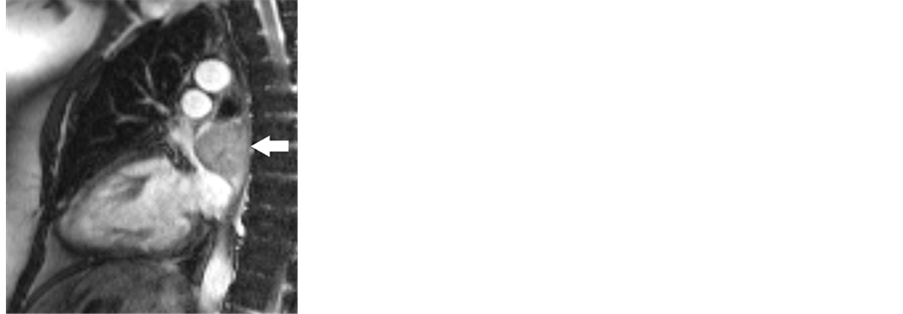

Further evaluation with dynamic heart MRI (Figure 2) was performed and did not show involvement of the atrial wall, however, the inhomogeneity and intense vascularization indicated a neurogenic tumor. Surgical excision was planned as the next diagnostic and simultaneously therapeutic step.

Figure 2. Pre-operative dynamic MRI: T1-weighed coronal section and T2-weighed oblique sagittal section.